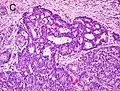

-

Gleason score 6 (3+3) -

Cribriform pattern: Gleason grade 4 -

Gleason score 7 (3+4) with minor component of cribriform glands -

Gleason score 8 (4+4) with glomeruloid glands -

Gleason score 8 (4+4) with irregular cribriform glands -

Gleason score 8 (4+4) with fused glands with cytoplasmic vacuoles -

Gleason score 8 (4+4) with poorly-formed glands -

Gleason score 9 (4+5) with cribriform glands, some with necrosis -

Gleason score 10 (5+5) with cords of cells -

Gleason score 10 (5+5) with individual cells -

Gleason score 10 (5+5) with solid sheets of cells